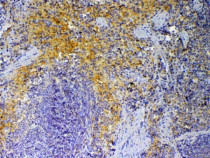

ARG43362 anti-CXCL4 / PF4 antibody IHC-P image

Immunohistochemistry: Paraffin-embedded Mouse spleen tissue. Antigen Retrieval: Heat mediation was performed in Citrate buffer (pH 6.0) for 20 min. The tissue section was blocked with 10% goat serum. The tissue section was then stained with ARG43362 anti-CXCL4 / PF4 antibody at 1 µg/ml dilution, overnight at 4°C.